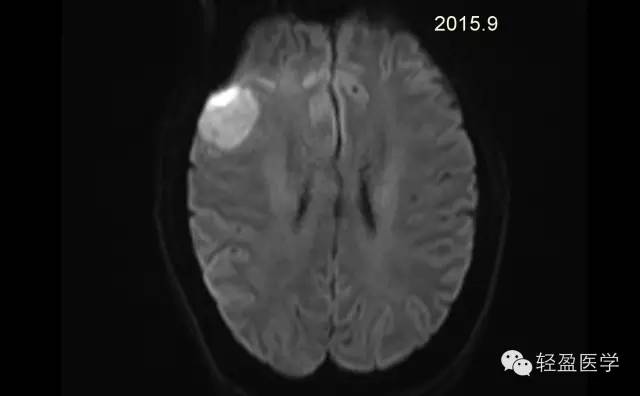

【病例】颅内肿瘤,脑内?脑外?

病理为:小细胞恶性肿瘤,考虑为(外周)原始神经外胚层肿瘤,(复发)。以下是病例结果及分析。